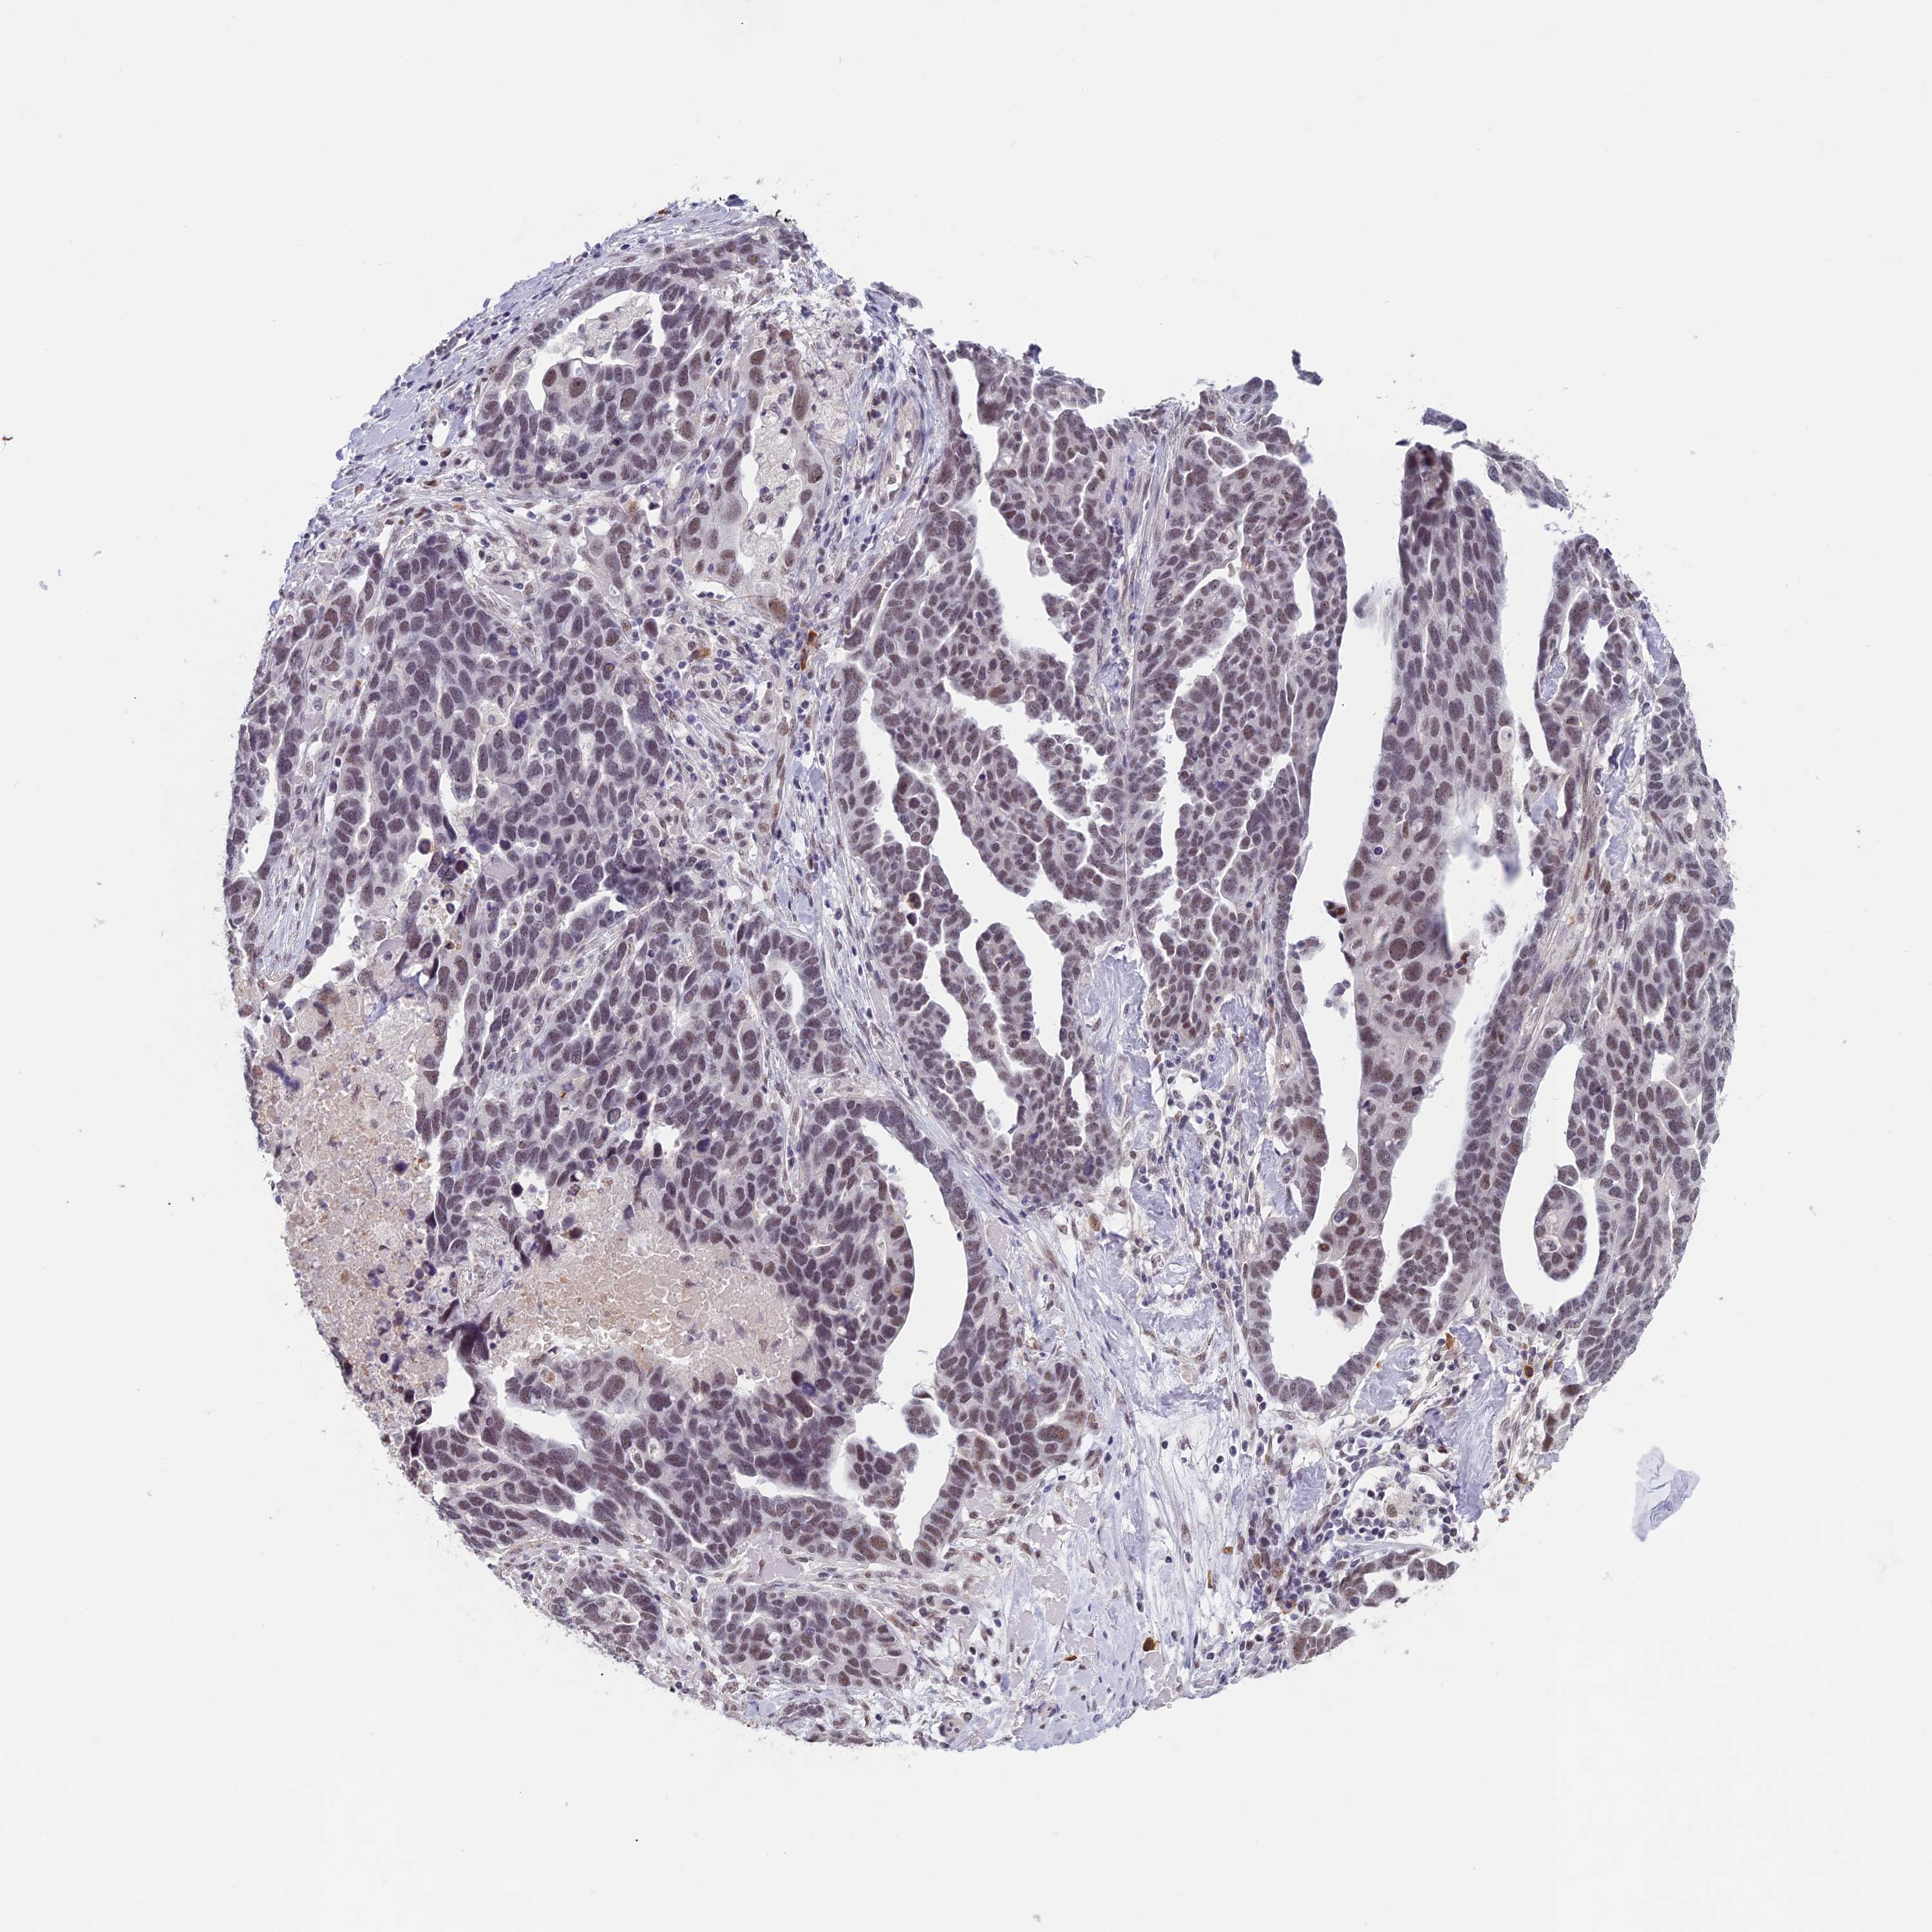

OVARIAN CANCER - Protein expressioni

A mouse-over function shows sample information and annotation data. Click on an image to view it in a full screen mode. Samples can be filtered based on level of antibody staining by selecting one or several of the following categories: high, medium, low and not detected. The assay and annotation is described here.

Note that samples used for immunohistochemistry by the Human Protein Atlas do not correspond to samples in the TCGA dataset.

Antibody stainingi

Antibody staining in the annotated cell types in the current human tissue is reported as not detected, low, medium, or high, based on conventional immunohistochemistry profiling in selected tissues. This score is based on the combination of the staining intensity and fraction of stained cells.

Each image is clickable and will lead to virtual microscopy that enables deeper exploration of all samples and also displays staining intensity scores, fraction scores and subcellular localization as well as patient and tissue information for each sample.

Antibody HPA042360

Staining

High

Medium

Low

Not detected

Intensity

Strong

Moderate

Weak

Negative

Quantity

>75%

75%-25%

<25%

None

Location

Nuclear

Cytoplasmic/membranous

Cytoplasmic/membranous,nuclear

Cystadenocarcinoma, serous, NOS

Carcinoma, endometroid

Cystadenocarcinoma, mucinous, NOS

Carcinoma, NOS